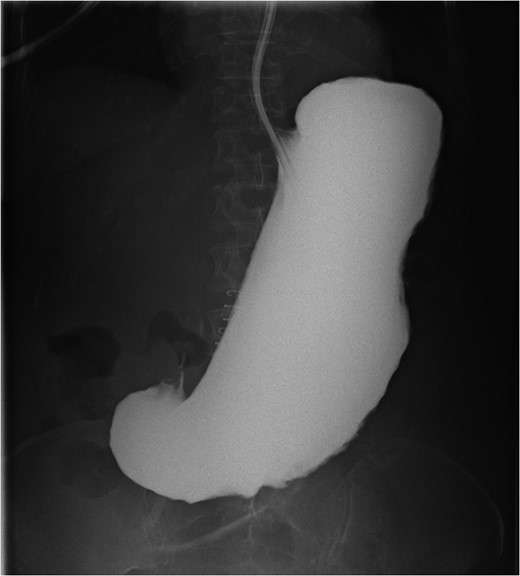

A 63-year-old cachectic female with a medical history of multiple myeloma and advanced amyloidosis was admitted to our institution with complaints of left lateral thigh pain and nausea. At the time of presentation, her myeloma and associated vertebral fractures were under active treatment with cyclophosphamide and bortezomib. Ibuprofen had been prescribed 10 days prior to admission for musculoskeletal pain. The patient’s nausea was associated with increasing abdominal distention over approximately 3 months. Computerized axial tomography performed on admission (Fig. 1) demonstrated a dilated stomach containing fecalized material. The patient reported passing gas and stool. She was placed on a general diet and was managed without nasogastric decompression as per her medical team. She continued to receive ibuprofen and was treated with pulse dose steroids, cyclophosphamide and bortezomib until hospital day 5 when the patient complained of sudden, severe abdominal pain.

Computed tomography scan at presentation (prior to perforation) demonstrating gastric distention secondary to amyloid provoked gastroparesis with fecalization of gastric contents.